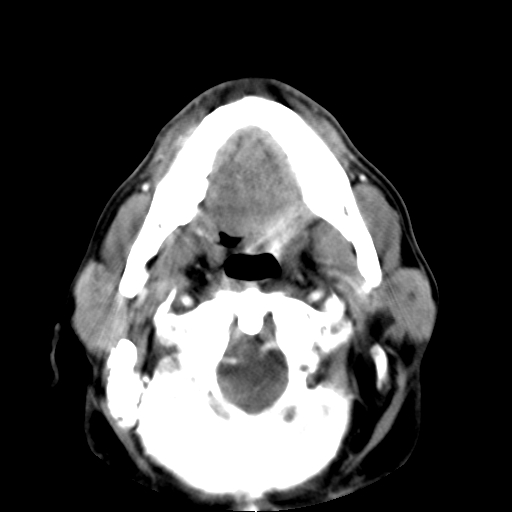

标题: CT24019:男,45岁,发现颈部肿物5个月。 [打印本页]

男,45岁,发现颈部肿物5个月,彩超示:双侧颈部及下颌部软组织增厚。

考虑双侧颈项部良性对称性脂肪增多症。